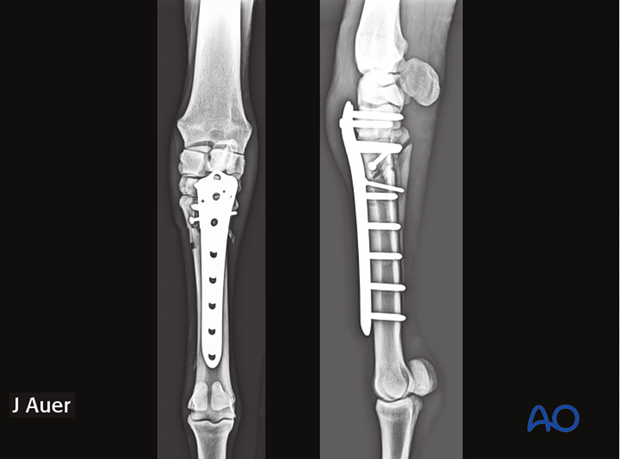

The fracture is anatomically reduced and repaired with one or two plates spanning the entire bone and applied at 90° relative to each other (left). In small ponies, some foals and selective cases of adult horses only one plate may be selected (right).

Alternate possibilities are any of the human condylar plate, which either are stronger (left) or allow the placement of multiple screws in a widened area of one plate end.